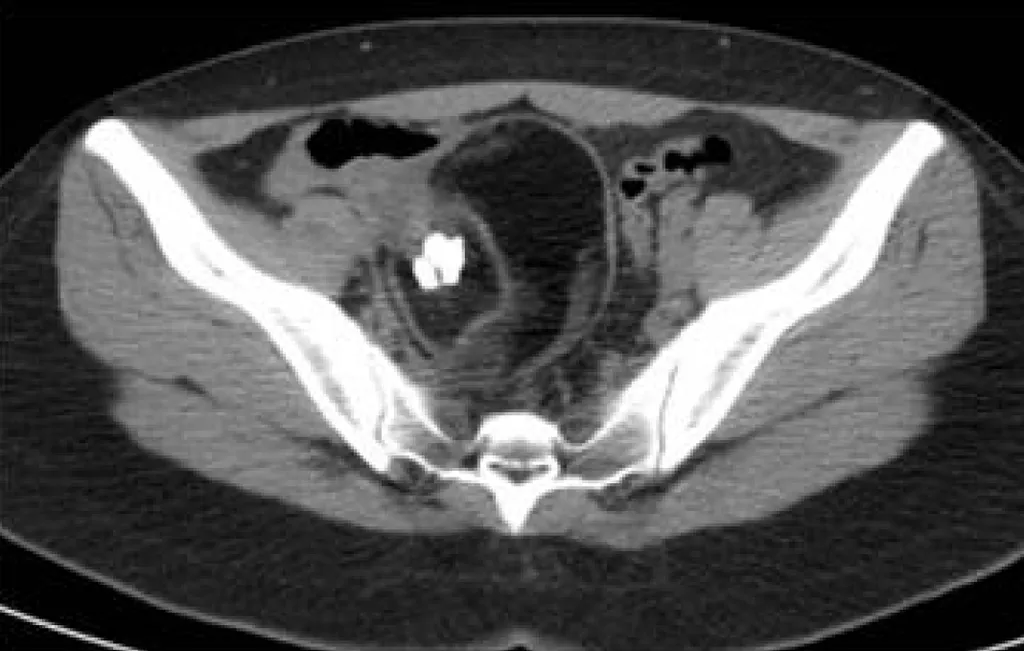

詳解

破題關鍵

圖片中下腹部病灶內有明顯的脂肪密度(較暗區塊)和高密度鈣化(非常亮白,形狀不規則,像骨頭或牙齒),這是畸胎瘤的典型影像特徵。

選項拆解